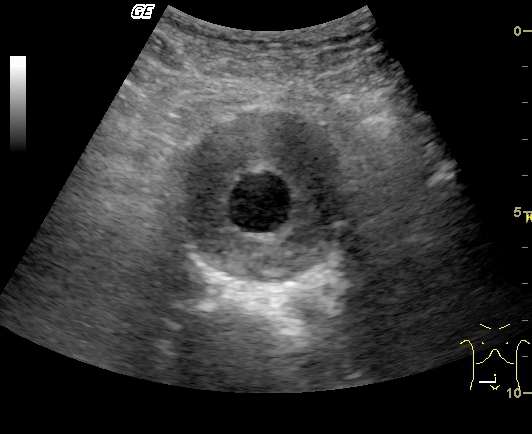

Заблуждения и факты о внутрибрюшной беременности